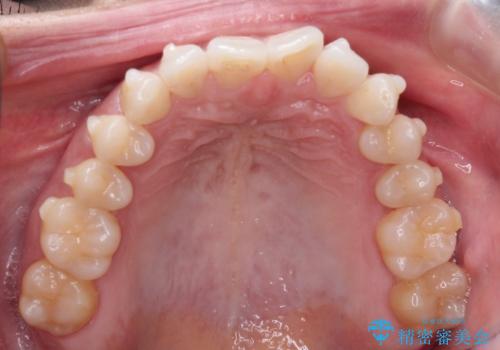

前歯のがたつきと隙間の矯正 インビザラインにて

- 上顎の前歯のがたつきと、下の前歯の隙間を主訴に来院されました。

下の前歯が先天的に欠損していました。

上顎の歯と歯の間をわずかに削りスペースを作り、ガタガタの改善し、下顎の前歯は隙間を閉じる計画としました。

非常に協力的な患者様でしたので、早期に治療が終了することができました。